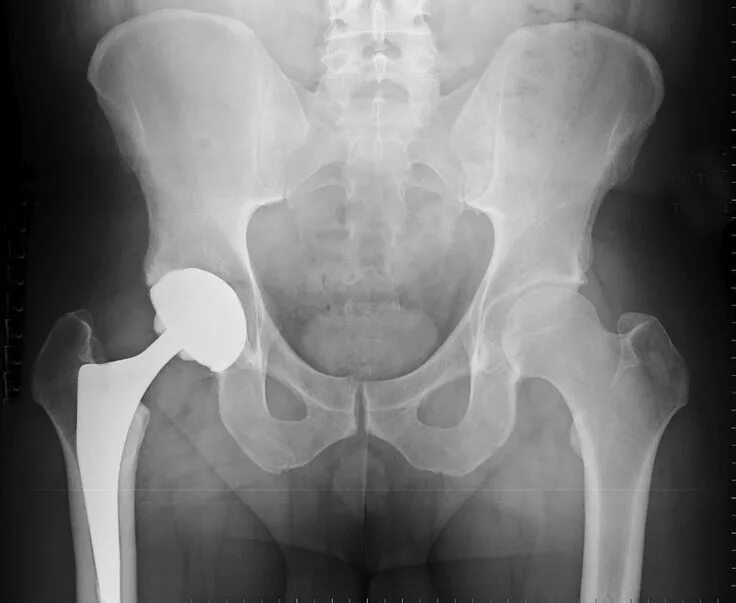

Горяев тазобедренного сустава